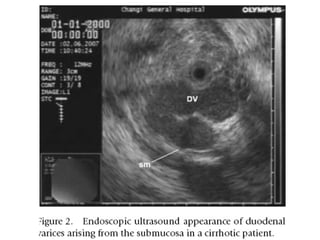

Periduodenal Collaterals